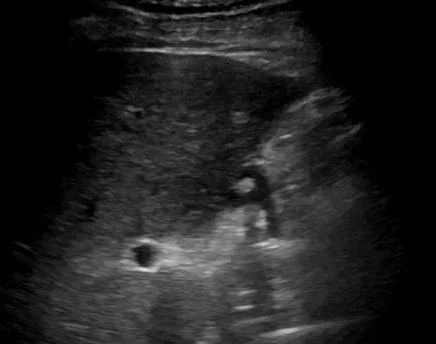

A 64 y.o. male comes to the ED with abdominal pain and hypotension.

you notice some gallstones ....and

and a discontinuity at the end of the gall bladder.  What happened?

Our patient had a rupture of the gallbladder with stones spilling out into a cavity under the liver. The reason the stones were not free in the abdomen was because of adhesions found at surgery.